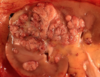

What type of cancer is seen here?

• KEY Features?

• what would you expect to see on microscopic examination?

Renal Clear Cell Carcinoma

• Key Features

• solitary, well defined, polar

• YELLOW, cysts , necrosis, HEMORRHAGE

MICROSCOPIC FEATURES:

• Clear LIPID FILLED cells with CHICKEN WIRE vessel formation found between the cells

How does a Renal Cell tumor present grossly?

• Hemorrhage and Necrosis are common - hemorrhage most likely related to highly vascularized tissue arising from VHF mutations leading to HIF-1alpha and ultimately VEGF release